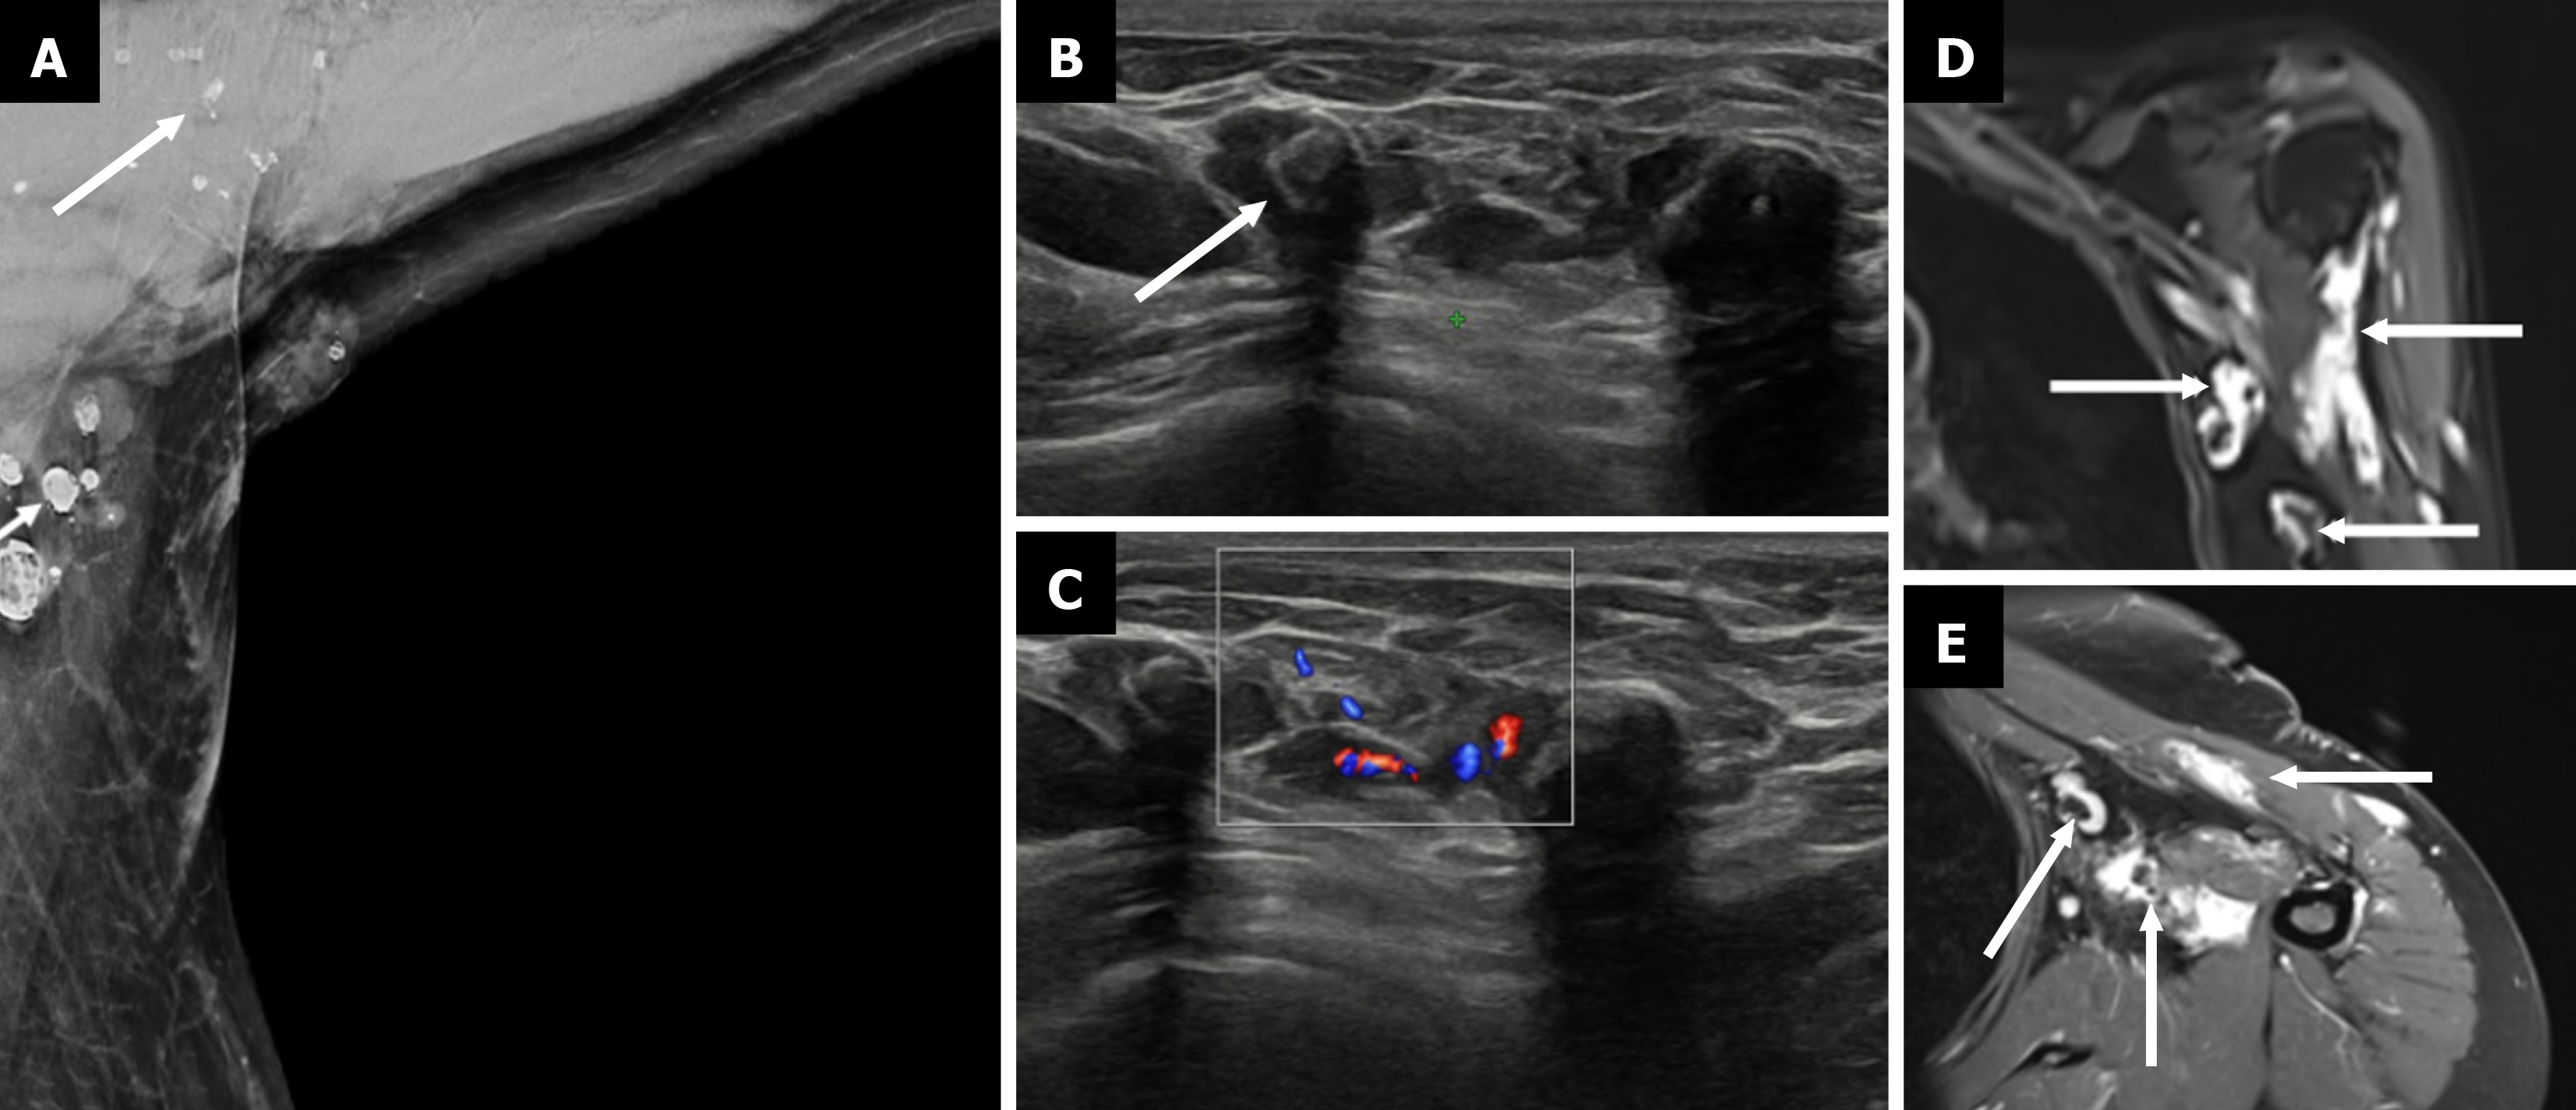

Figure 12  Venolymphatic malformation.

A: Mediolateral oblique mammogram with an axillary view shows multiple well-defined, lobulated densities in the axilla (arrow), some containing coarse calcifications; B: Grayscale ultrasound reveals multiple anechoic and hypoechoic compressible tubular channels in the subcutaneous plane with echogenic phleboliths (arrow), which is consistent with dilated venous and lymphatic components; C: Color Doppler ultrasound demonstrates slow flow within some of the vascular channels; D: Coronal T2-weighted fat-saturated magnetic resonance image (MRI) shows hyperintense lobulated masses (arrows) in the axilla; E: Postcontrast axial T1-weighted fat-suppressed MRI shows enhancement of the lesion (thin arrows), with nonenhancing phleboliths, which is consistent with a benign low-flow vascular malformation.